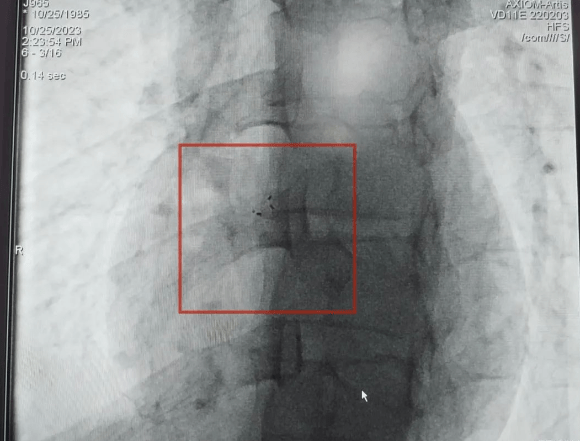

手术进行中

植入体内的封堵器